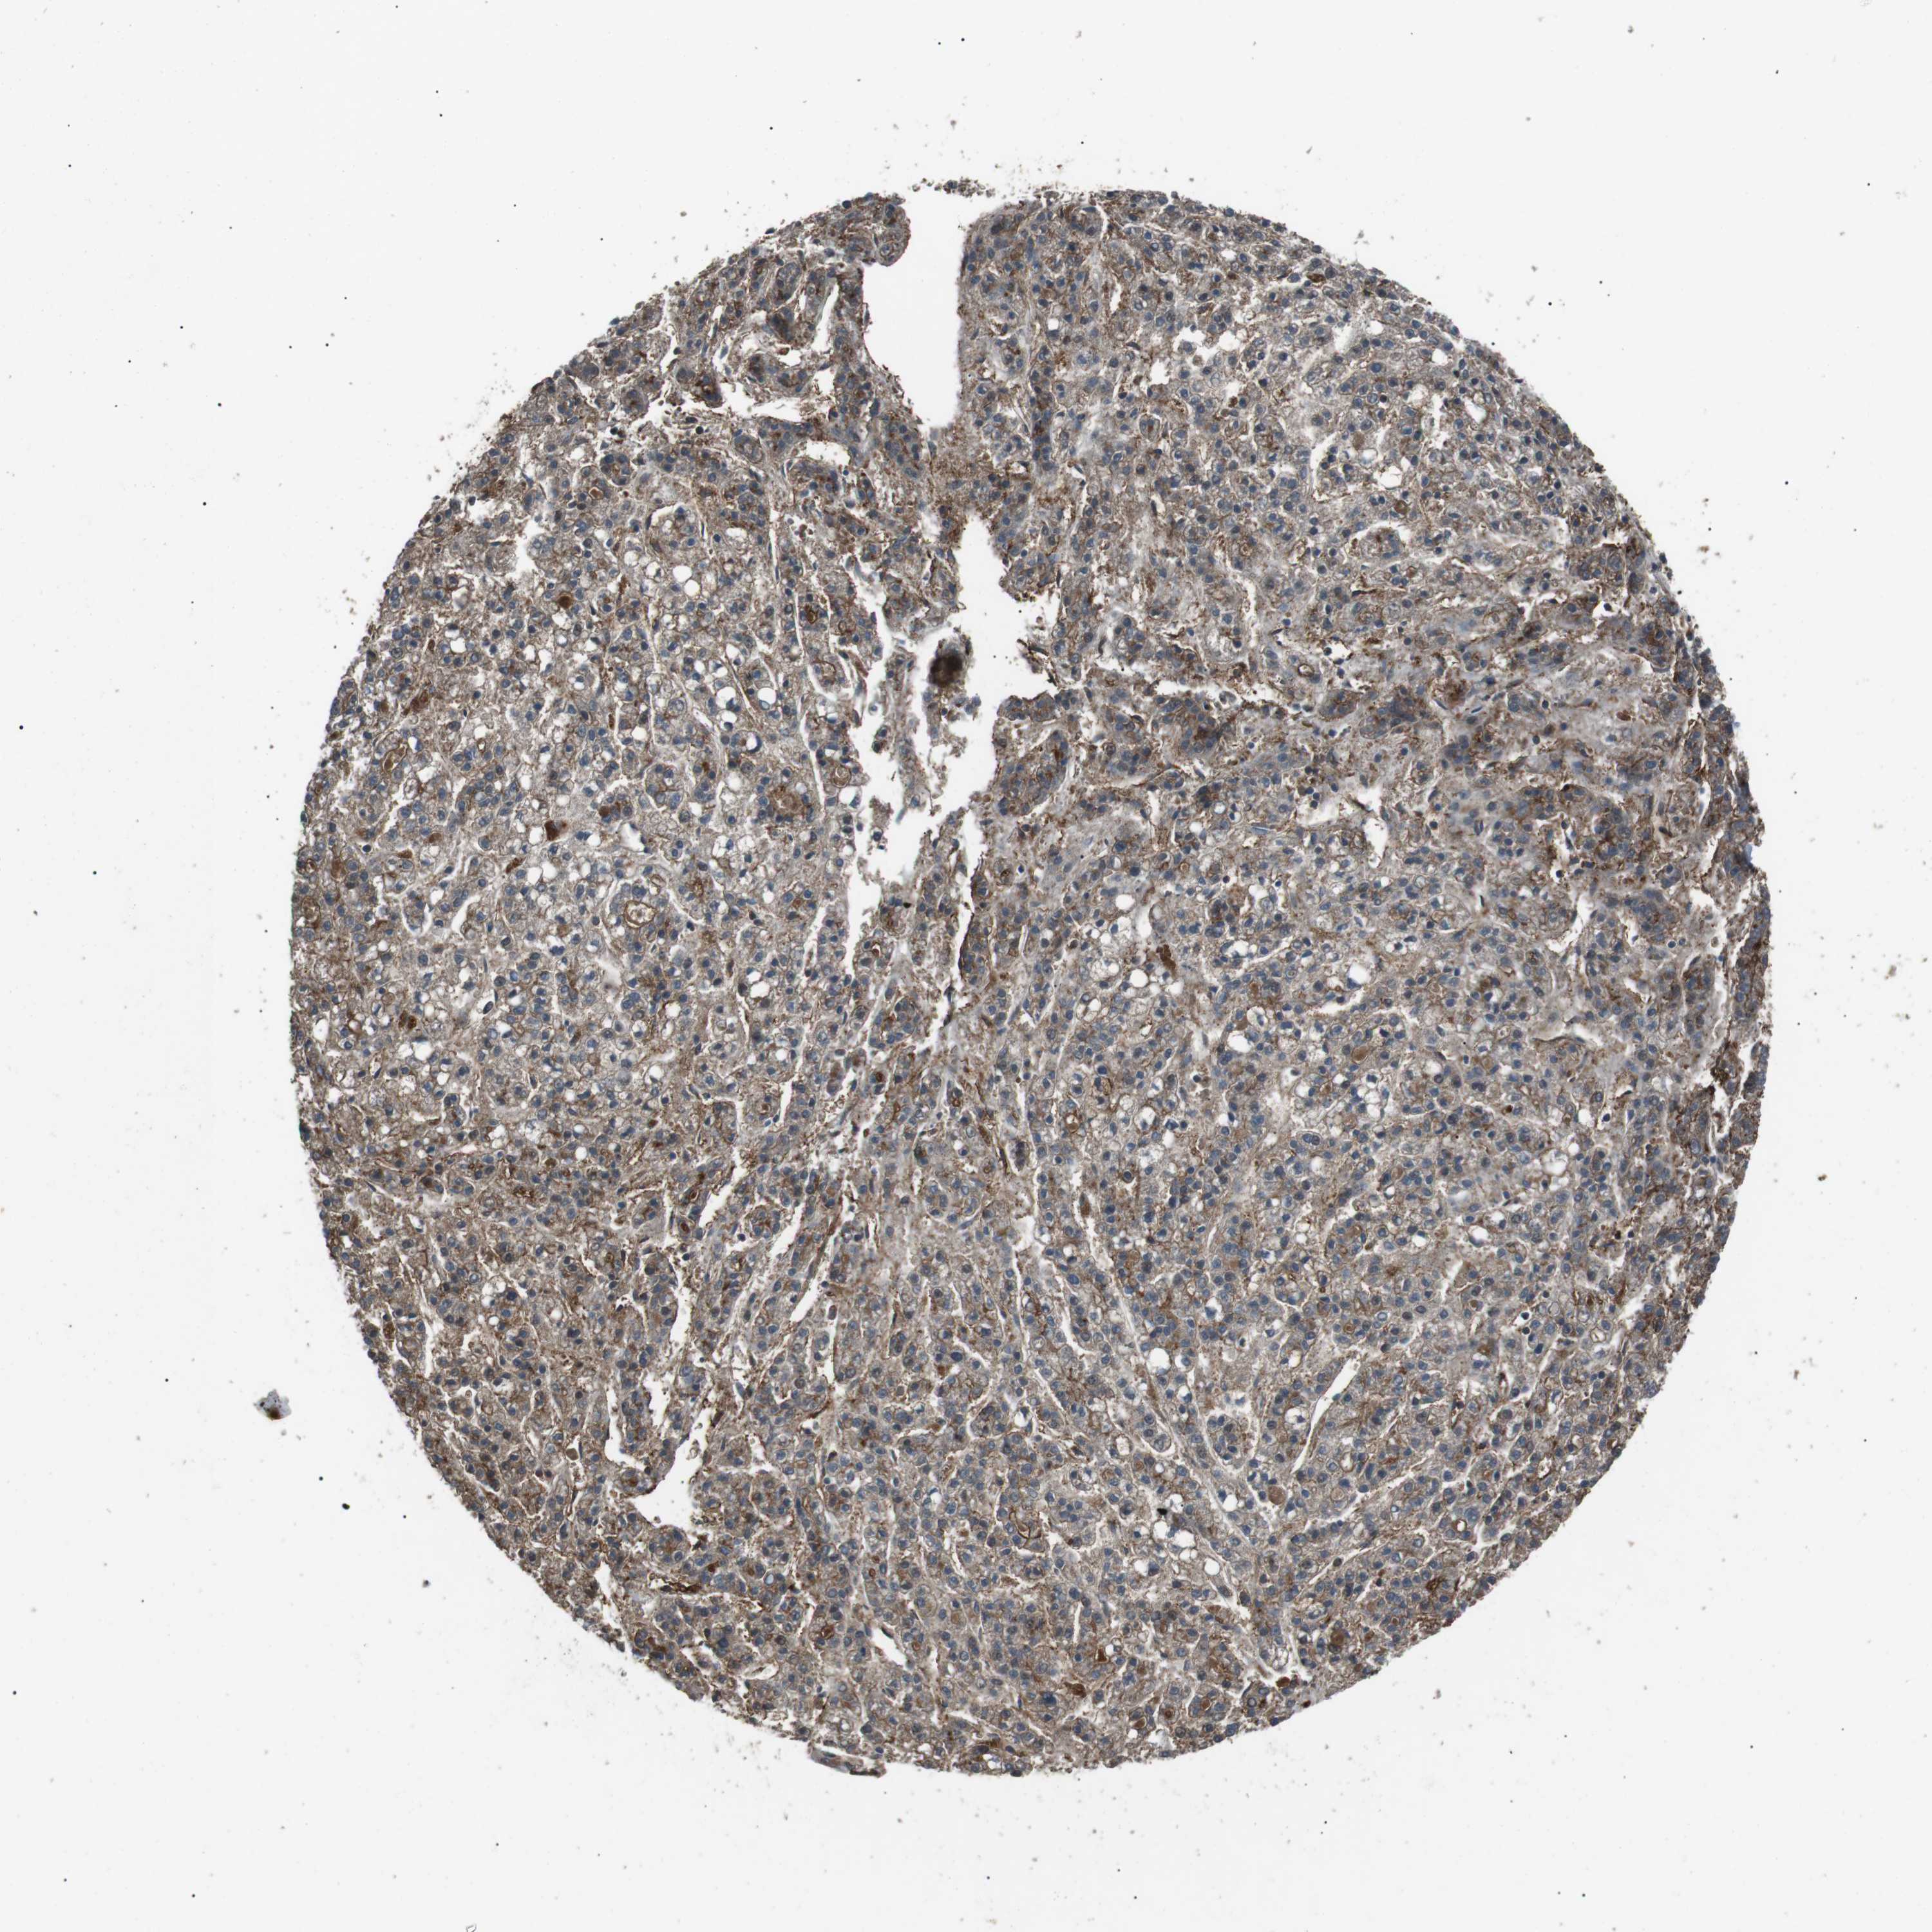

LIVER CANCER - Protein expressioni

A mouse-over function shows sample information and annotation data. Click on an image to view it in a full screen mode. Samples can be filtered based on level of antibody staining by selecting one or several of the following categories: high, medium, low and not detected. The assay and annotation is described here.

Note that samples used for immunohistochemistry by the Human Protein Atlas do not correspond to samples in the TCGA dataset.

Antibody stainingi

Antibody staining in the annotated cell types in the current human tissue is reported as not detected, low, medium, or high, based on conventional immunohistochemistry profiling in selected tissues. This score is based on the combination of the staining intensity and fraction of stained cells.

Each image is clickable and will lead to virtual microscopy that enables deeper exploration of all samples and also displays staining intensity scores, fraction scores and subcellular localization as well as patient and tissue information for each sample.

Antibody HPA015576

Staining

High

Medium

Low

Not detected

Intensity

Strong

Moderate

Weak

Negative

Quantity

>75%

75%-25%

<25%

None

Location

Nuclear

Cytoplasmic/membranous

Cytoplasmic/membranous,nuclear

Cholangiocarcinoma

Carcinoma, Hepatocellular, NOS